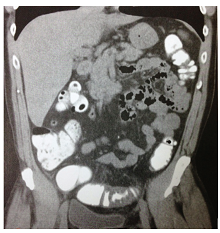

Observe a imagem a seguir.

Com base na imagem, pode-se firmar o diagnóstico de: